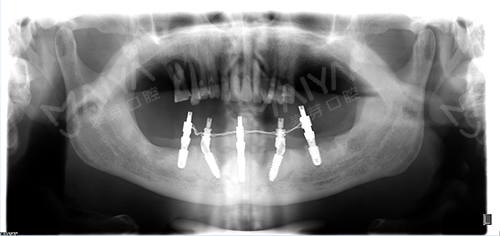

麦芽口腔院长指出,对于中老年群体,All-ON-4种植牙技术打破传统种植技术瓶颈,可以破解牙槽骨萎缩、骨量不足等种植难题,而且手术过程无需植骨,让老年缺牙群体也能实现快速种牙。对比传统的种植牙技术,大大减少就诊时间、减少痛苦和节省费用,实现患者当天种牙当天啃苹果。

种植5颗牙后口腔全景片

经过前期的牙周清洁、治疗后,根据李老口内实际情况,为达到更好的增加负重、增强咀嚼能力效果,麦芽口腔种植医师团队对ALL-ON-4种植技术进行升级和改造,为其量身定制了"ALL-ON-5"种植方案,治疗后总共恢复24颗牙齿。